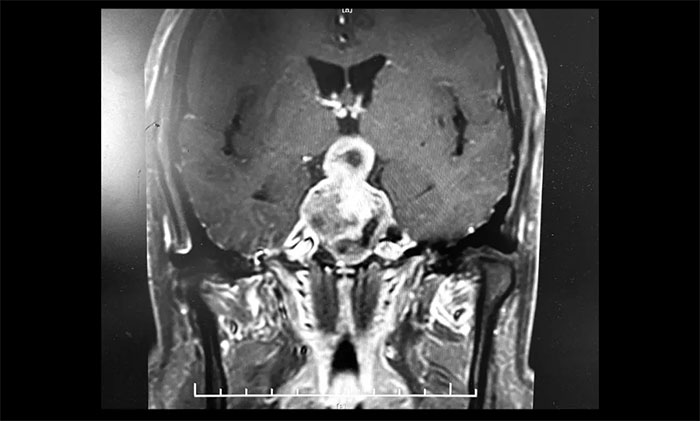

▲ 5公分巨大垂体瘤,呈“哑铃”形,李士其教授团队迎难而上顺利切除